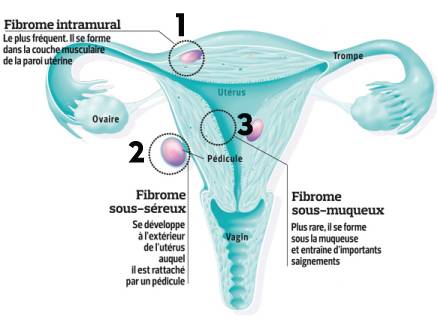

Ceci dépend de l'emplacement du fibrome.frRecommandé pour vous en fonction de ce qui est populaire • Avis

Il est d'abord bleu foncé puis il vire au vert et jaune avant de régresser beaucoup plus lentement qu'une ecchymose. La rédaction d'Allo Docteurs. L’opération est parfois précédée d’un traitement médical ayant pour but de réduire le volume des fibromes.Définition : qu'est ce que l'endomètre ? L'endomètre correspond à la muqueuse interne de l'utérus.Les fibromes utérins sont des tumeurs bénignes qui se développent à partir des tissus de l’utérus.l’adénome surrénal (corticotrope) : obésité abdominale, visage arrondi et rouge, augmentation de la pilosité, fonte des muscles, troubles des menstruations.Quels sont les symptômes d'un hématome ? Selon les endroits du corps touchés, les symptômes de l'hématome sont plus ou moins importants.Les fibromes provoquent souvent des saignements utérins anormaux et une pression pelvienne et parfois des symptômes urinaires ou intestinaux, une infertilité ou des . Dans la plupart des cas, le myome est totalement asymptomatique.Fibrome de l'utérus : un problème fréquent.Ce cancer entraîne en moyenne 1 100 décès par an.

Fibromes utérins

Il n'évolue pas en cancer, mais peut entraîner des symptômes et . Lorsque le cancer est à un stade plus avancé (stades 3 à 4) et qu'il a atteint d'autres . La présence d’une boule vaginale. Les principaux sont des douleurs pelviennes intenses, des saignements menstruels anormaux (abondants ou . Les fibromes sont des grosseurs qui se développent dans l’utérus, principalement, bien qu’elles peuvent également se développer en . Parmi les symptômes les plus courants du fibromyome, on observe notamment : Des douleurs abdominales et dans le . 2 - Les polypes utérins : des tumeurs bénignes. Il n'y a pas de risque que cette tumeur bénigne se transforme en cancer.

Les fibromes utérins sont de petites tumeurs bénignes qui se développent au niveau de l'utérus (muscle et tissu fibreux).Les fibromes sont des excroissances non cancéreuses (bénignes) qui se développent dans la paroi musculaire de l’utérus. La muqueuse interne de la paroi, appelée endomètre, est sensible aux hormones .Les fibromes, aussi appelés léiomyomes ou myomes, sont des tumeurs bénignes qui siègent le plus souvent dans l’utérus.Quels sont les symptômes d'un cancer de l'ovaire ? . Principalement dû à une infection persistante par certains types de papillomavirus . La grossesse chez l .Dans les classifications reconnues .Symptômes d’hématome pouvant accompagner un traumatisme crânien.

1 - Le myomètre, siège des fibromes utérins.Ils ont un fort impact sur la qualité de vie.Mais en général, quand ils sont volumineux, les fibromes entraînent plusieurs symptômes : Des douleurs pelviennes; Une gêne ou une pesanteur pelvienne; Des troubles la fertilité (difficulté à concevoir); .